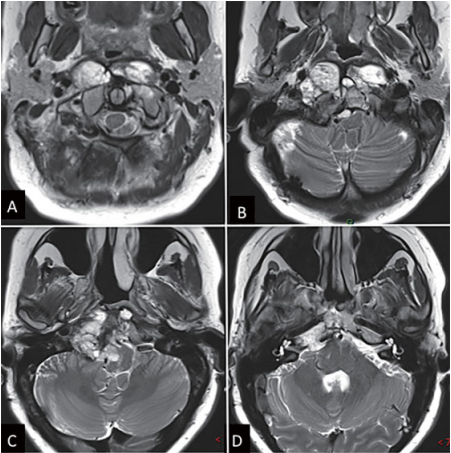

术前影像显示一个巨大脊索瘤

Carol在体检中发现颅颈交界区脊索瘤,历经4次手术和多次化疗仍未能遏制肿瘤向脑干、椎动脉等关键区域扩散,手术风险极高且多家医院拒绝再次治疗。面对这一危局,福教授创新采用经鼻内镜联合分阶段开颅手术,先经鼻切除中线肿瘤,再通过远外侧入路清除侧方病灶,在确保安全的前提下实现尽可能切除。